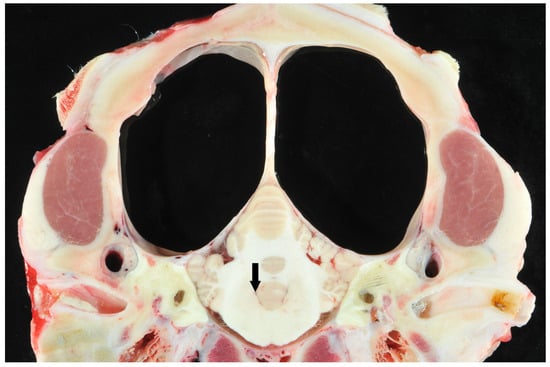

Eleven calves underwent MRI. Imaging identified different stages of cortical parenchymal loss affecting both white and gray matter throughout the hemispheres in all 11 calves (Table 1). The cerebral hemispheres were reduced to a thin rim of tissue in six cases. The remaining cavity was filled with cerebrospinal fluid by a secondary enlargement of the lateral ventricles (Figure 2). These findings are consistent with hydranencephaly. In three cases, there was a severe enlargement of the ventricular dimensions and residual gyrated cerebral tissue was visible, consistent with severe internal hydrocephalus (Figure 3). Two calves showed no or only mild ventricular enlargement with normal gyration of the cerebral tissue. In these two cases, a reduced contrast between white and gray matter was noticeable and focal hyperintense areas in the white matter were visible. Impaired cerebral myelination or focal leukomalacia were suspected.

4.7. Postmortem Results

Figure 4. Transverse section of the scull of a calf at the level of the cerebellar vermis and pyramid with suspected hydranencephaly. Note the dilated ventricles and the surrounding small pial rim without visible cortical structures (large clear spaces) and normal cerebellum. The fourth ventricle was not dilated (arrow).